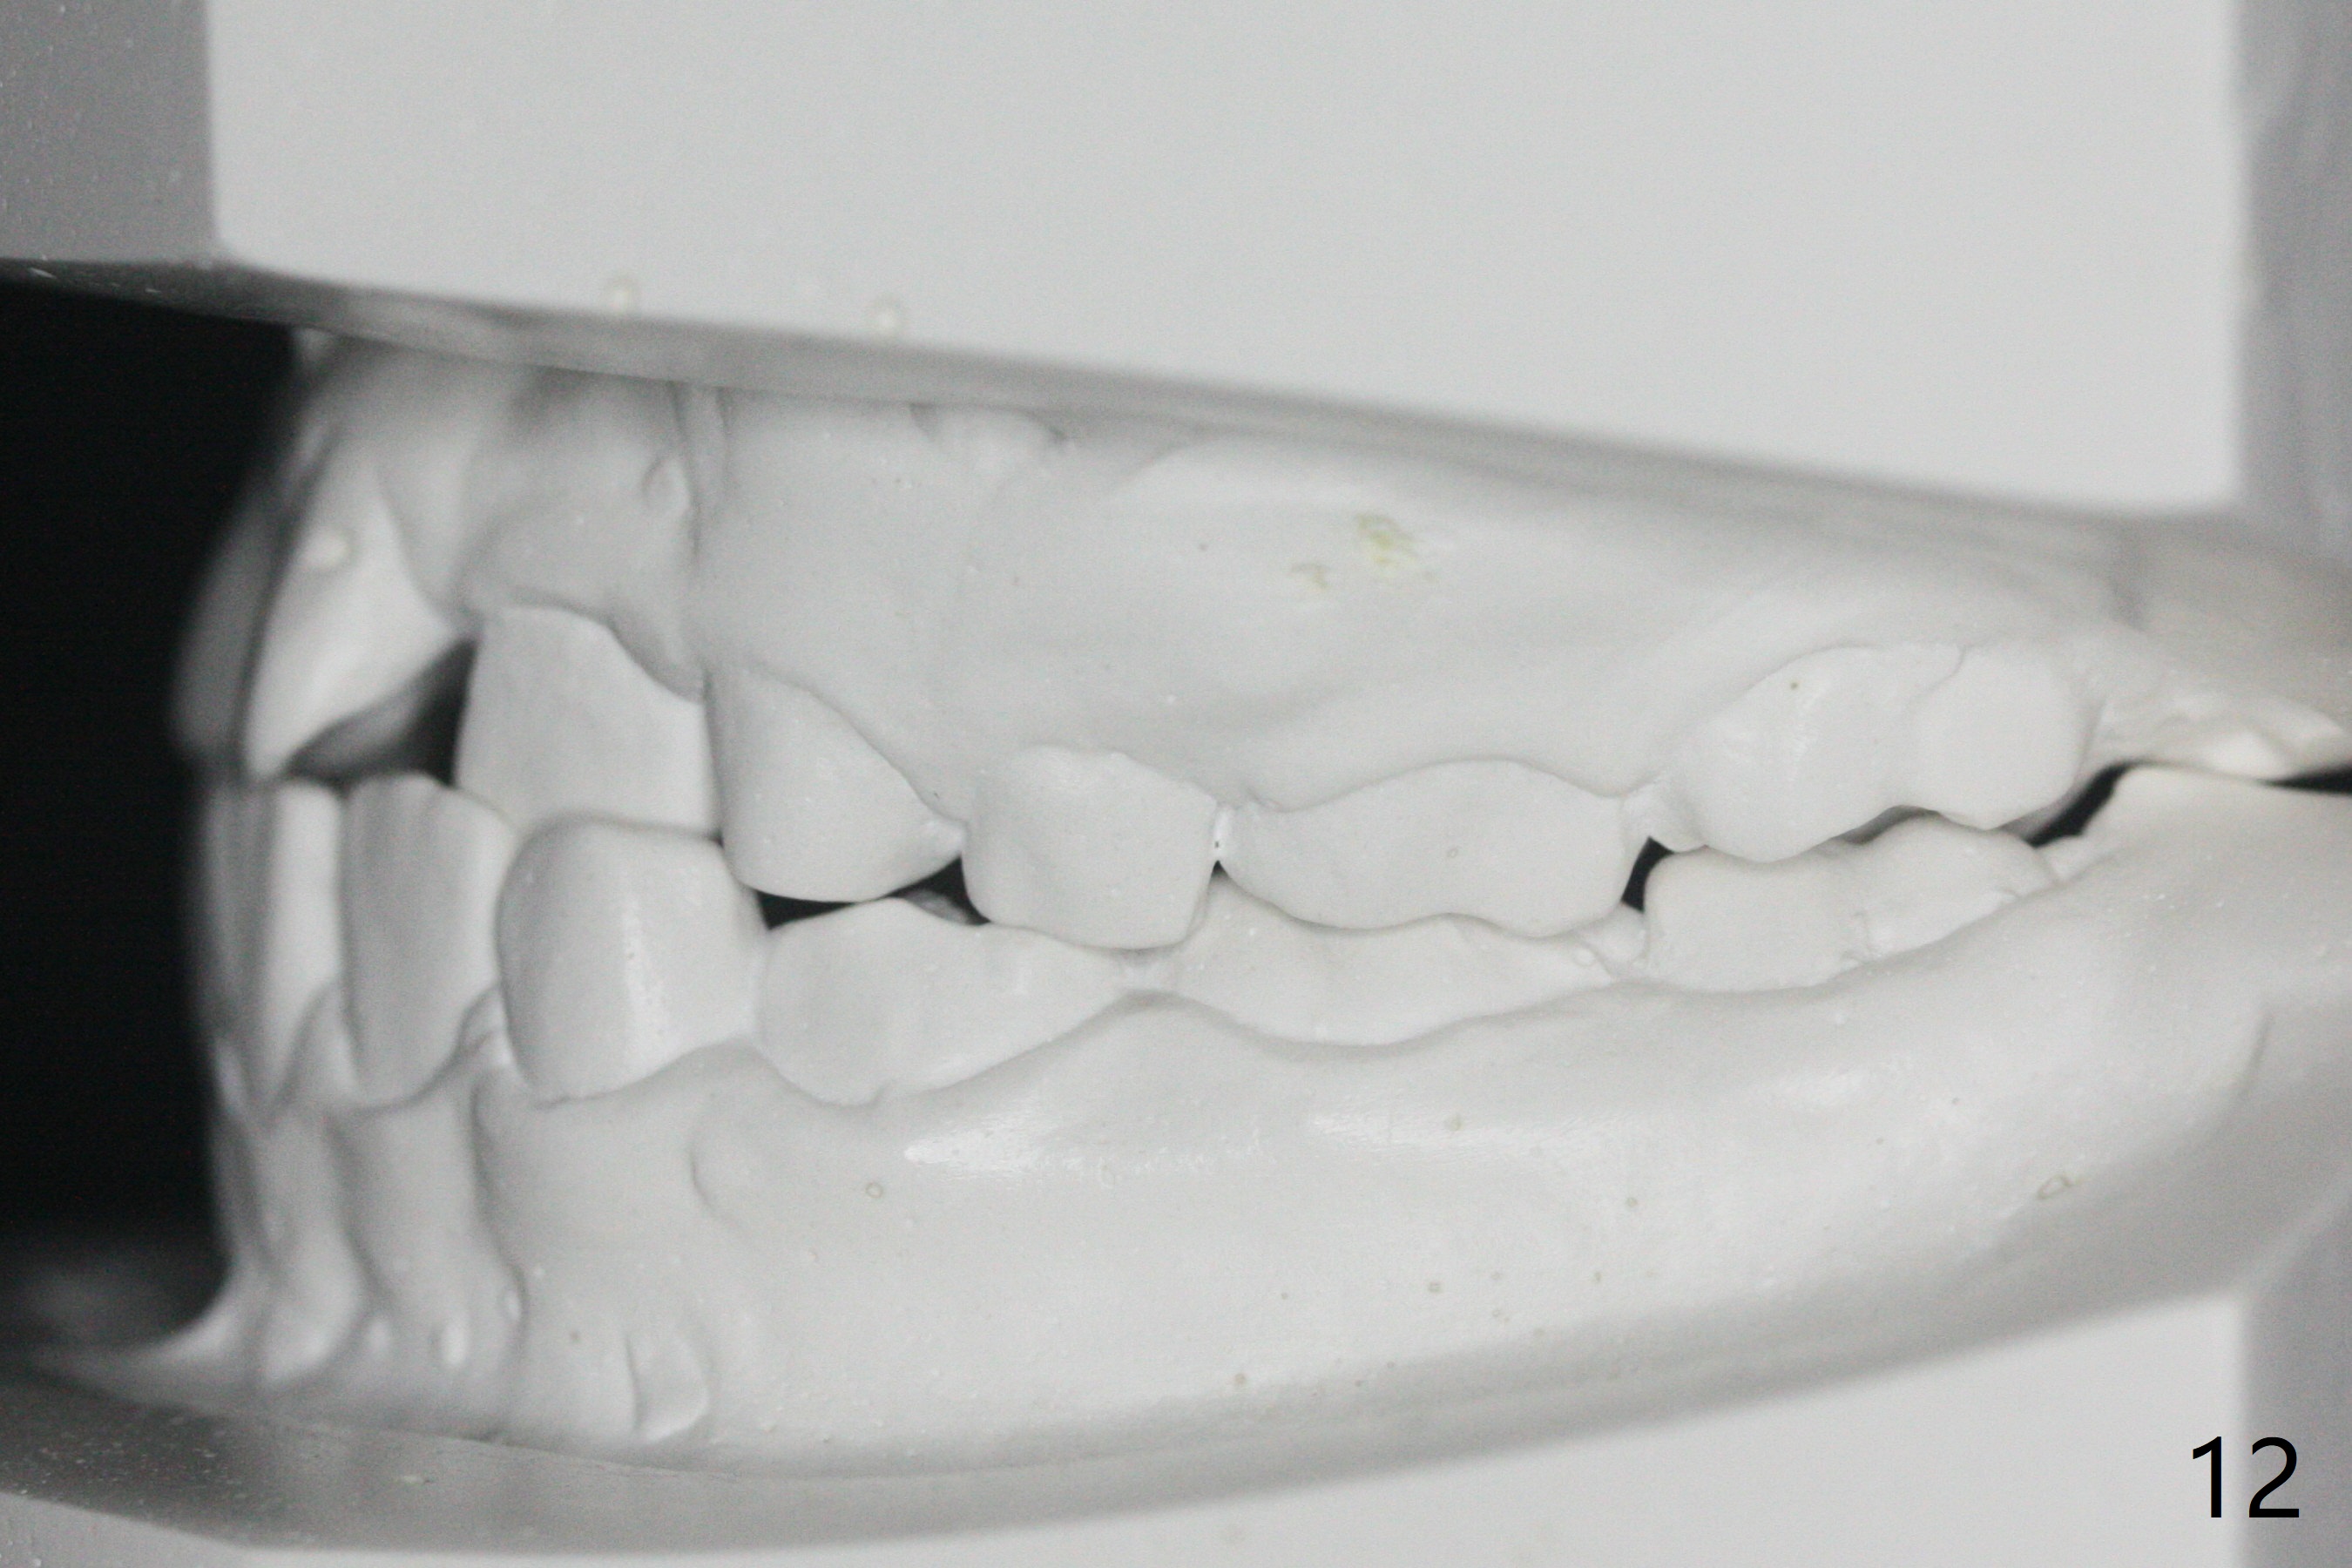

7岁女孩龋齿(图一)到八岁发展的严重(图二,三 (D))。为了有完整支抗,利用树脂(而不是不锈钢牙冠)保留左上第一乳磨牙(图六:D),以后可以安置矫正器。面部匀称(图七至十)。乳尖牙,第一恒磨牙:第一类咬合(图十一,十二)。左上前牙拥挤比右边轻,因为左上D龋齿破坏(图十三:D)。前牙扩弓时,右上D近中需要片切(^)。下颌拥挤轻(图十四),矫正器可以迟放置。